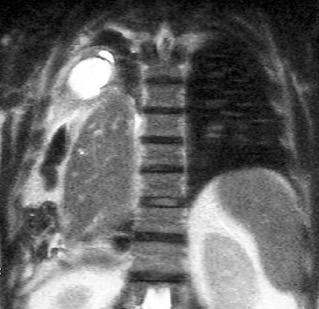

Nódulos pulmonares múltiples. (flechas verdes). Masas paratraqueales. (flechas amarillas). Dudoso ensanchamiento retrocrural (flechas negras). sigue….

Ttawfik A et al. Trans-diaphragmatic Pathologies: Anatomical Background and Spread of Disease on cross-sectional Imaging. Current Problems in Diagnostic Radiology. 2021.

T. mixto de células germinales del testículo

izquierdo Metástasis pulmonares. (flechas verdes). Ganglios paratraqueales. (flechas amarillas). Ganglios retroperitoneales (flechas negras)

Tawfik A et al. Trans-diaphragmatic Pathologies: Anatomical Background and Spread of Disease on cross-sectional Imaging. Current Problems in Diagnostic Radiology. 2021.